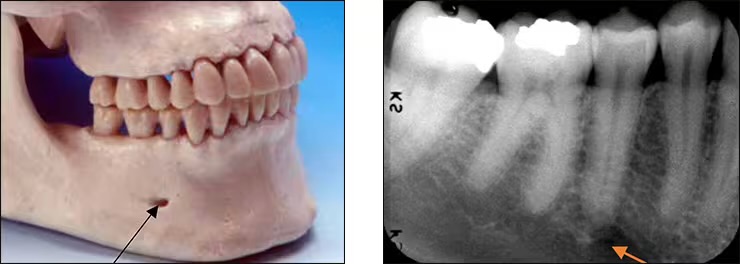

Mental foramen

Located below roots of mandibular premolars.

Is the opening for passage of the mental nerve and vessels.

Often misinterpreted as periapical lesions

Mandibular canal

Pathway in the bone where the inferior alveolar nerve and blood vessels flow through the mandible.

Extend from mandibular foramen within the ramus to the mental foramen.

Appears radiopaque